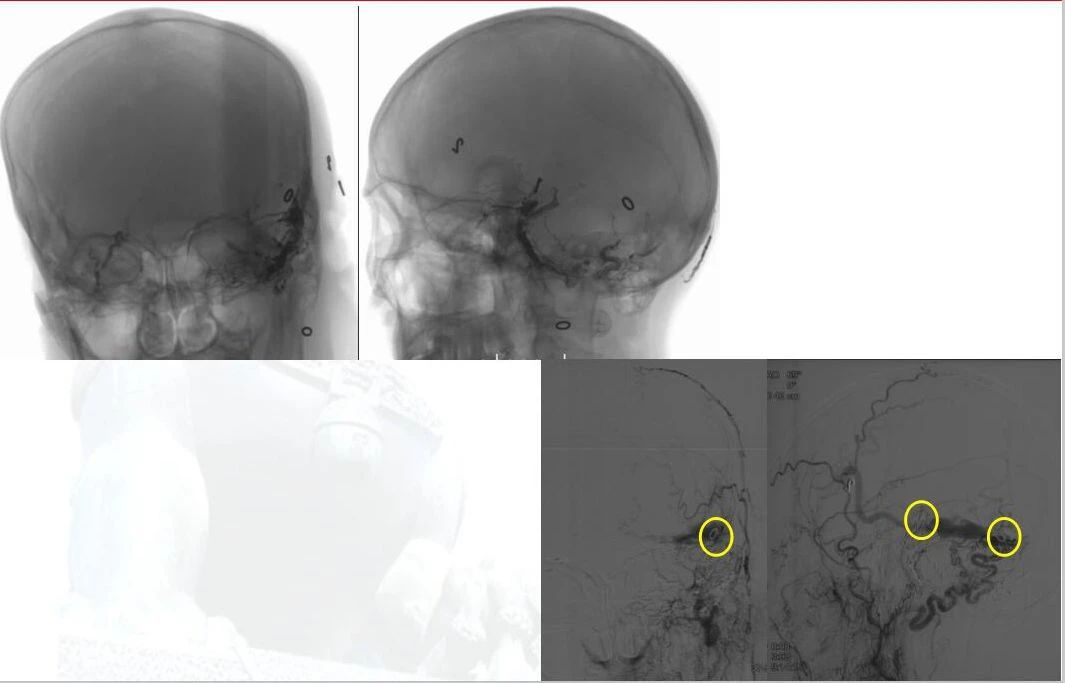

▲ 术前定位